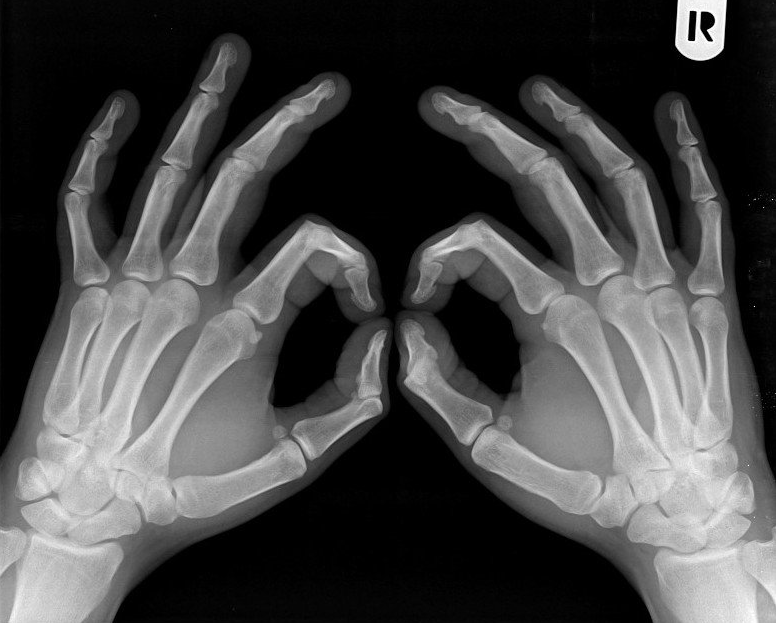

Secția trei – Radiologie

Atunci când te trimite doctorul la secția de radiologie, intri în panică. Nu înseamnă doar o călătorie în spațiu, ci și în timp, pentru că acolo timpul s-a oprit. Dacă vrei să ajungi la secția de radiologie, trebuie să treci prin partea de est a curții interioare a spitalului, să ocolești clădirea maternității și here […]